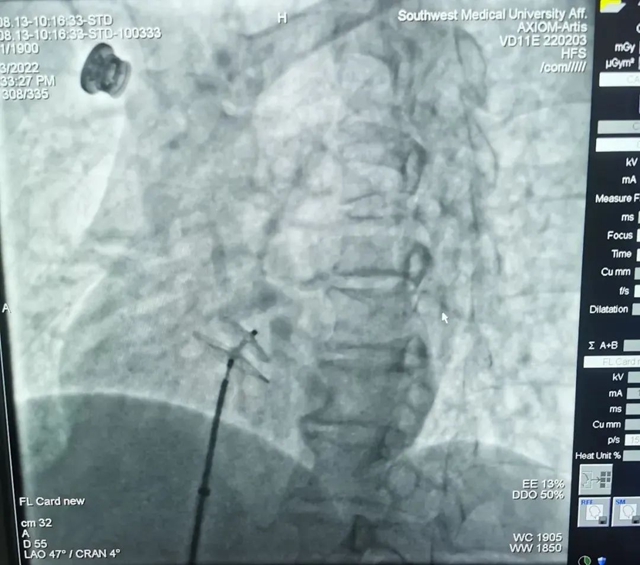

8月13日,心血管内科副主任罗钢教授带领心血管介入团队为刘大姐实施了卵圆孔未闭介入封堵术。手术过程非常顺利,用时不到一个小时,术后复查相关检查未见异常,后期恢复良好。